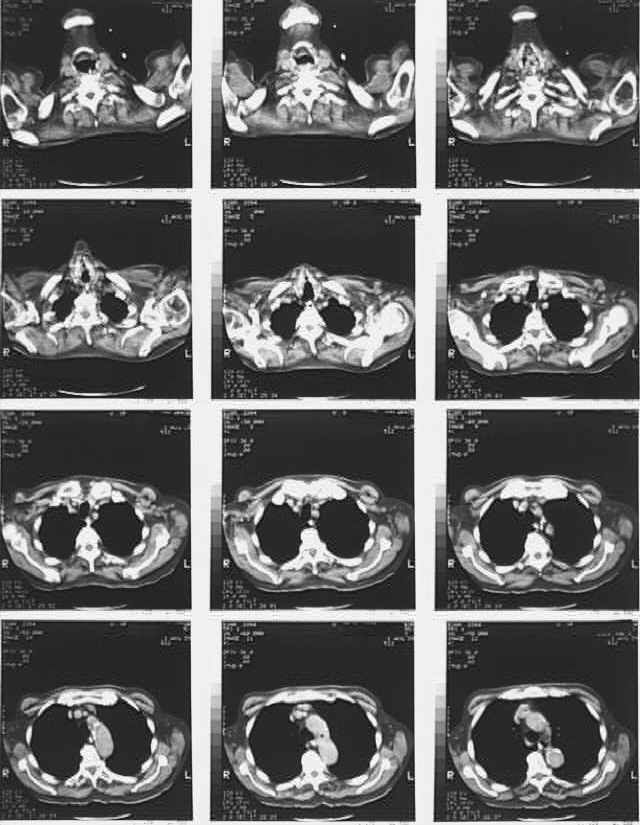

Radiology Images

Thorax- Chest CT Aug 1